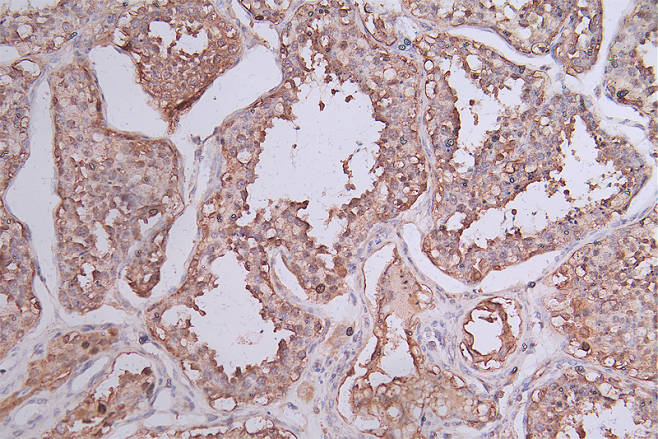

IHC image of CSB-RA644510A0HU diluted at 1:50 and staining in paraffin-embedded human rectal cancer performed on a Leica BondTM system. After dewaxing and hydration, antigen retrieval was mediated by high pressure in a citrate buffer (pH 6.0). Section was blocked with 10% normal goat serum 30min at RT. Then primary antibody (1% BSA) was incubated at 4°C overnight. The primary is detected by a Goat anti-rabbit polymer IgG labeled by HRP and visualized using 0.74% DAB.